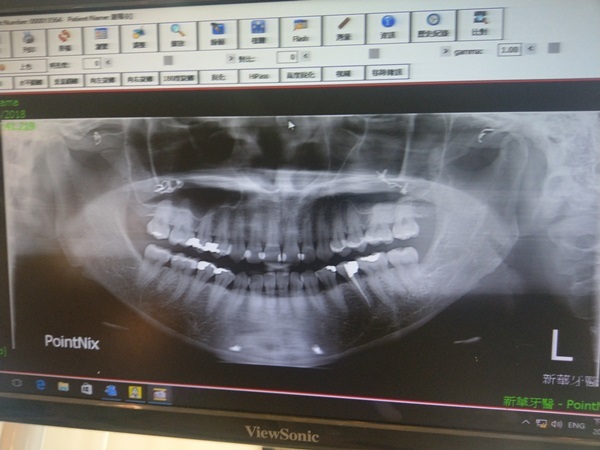

照X光前小護士替我在3D電腦斷層掃描儀咬合器上套上一個新的咬合套方便衣衣可以做口腔咬合拍攝,

雖然平時牙齒照顧得很好可是斷層掃描一照還是藏不住衣衣過去好幾顆蛀牙>///但卻也偷偷發現新華牙科在衛生環境上要求很嚴謹,

檢查口腔前雅詩醫師先針對剛剛拍攝的X光片口內狀況一一詳細解釋,

連過去做過根管治療的臼齒也難逃雅詩醫師法眼,

那顆小臼齒在高中時就已經做過根管治療,

只是經過時間變化補過的地方當然越來越大,

這回做冷光美白前雅師醫師還稍微再幫衣衣詳細檢查過呢!